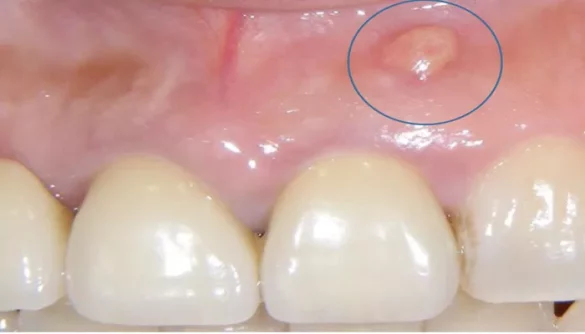

A gum abscess, also known as a periodontal abscess, is an infection that typically forms at the base of a tooth or around the gum tissue. It happens when bacteria invade the gum tissues, leading to inflammation and the formation of pus. The infection may start small but can rapidly become more severe without treatment.

Abscesses can also occur in other parts of the mouth, such as the roots of the teeth (periapical abscess), but gum abscesses specifically affect the soft tissues around the teeth. These abscesses often cause discomfort, redness, swelling, and, in some cases, fever.